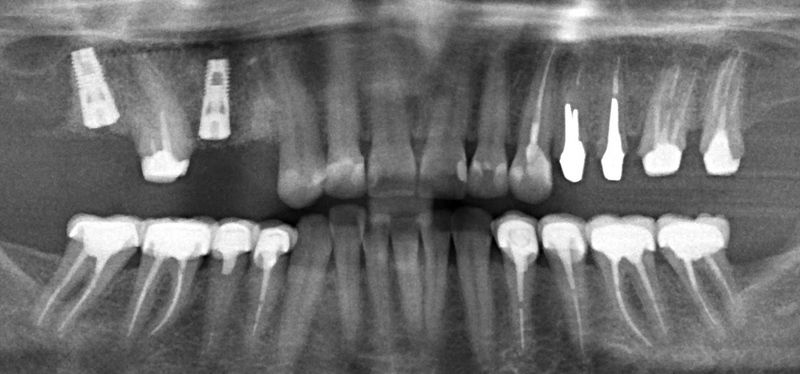

Рентген

Проведем комплекс исследований и сформируем план лечения